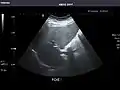

Left kidney

Kidneys: Right and left kidneys measure 11.5 cm and 12 cm in length respectively. No hydronephrosis. Small left lower pole kidney cyst.